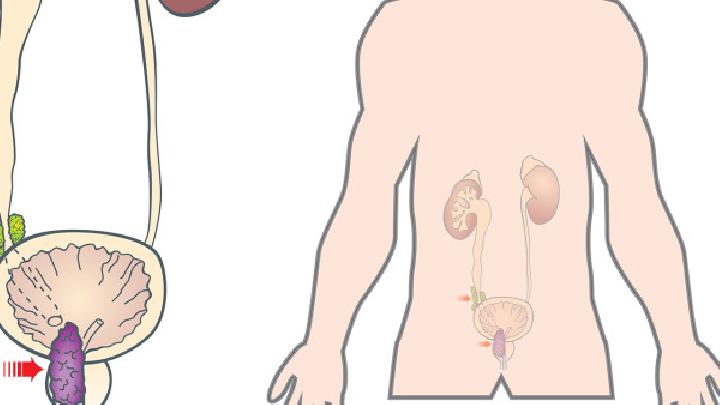

为什么老是觉得想尿尿

频繁出现尿意可能与饮水过量、膀胱过度活动症、尿路感染、前列腺增生、糖尿病等因素有关。建议及时就医明确病因,避免延误治疗。1、饮水过量短时间内摄入过多水分会导致尿液生成增加,膀胱充盈速度加快。这种情况无须特殊处理,调整每日饮水量至1500-2000毫升,避免睡前两小时大量饮水即可缓解。观察尿液颜色呈淡黄色时说明饮水量适中。2、膀胱过度活动症膀胱肌肉异常收缩会引...